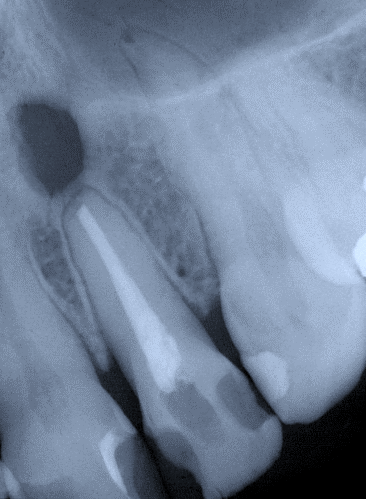

3. (Select ONE OR MORE correct answers)

The radiograph shows evidence of